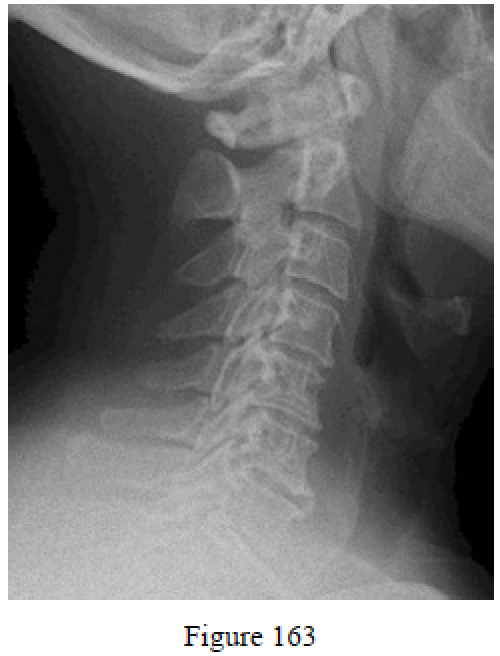

Question 163

Figure 163 is the lateral radiograph of a 67-year-old man with a long-standing history of neck pain. He slipped and fell in his bathtub, which resulted in a hyperextension injury to his cervical spine. What is the most likely spinal cord injury in this scenario?